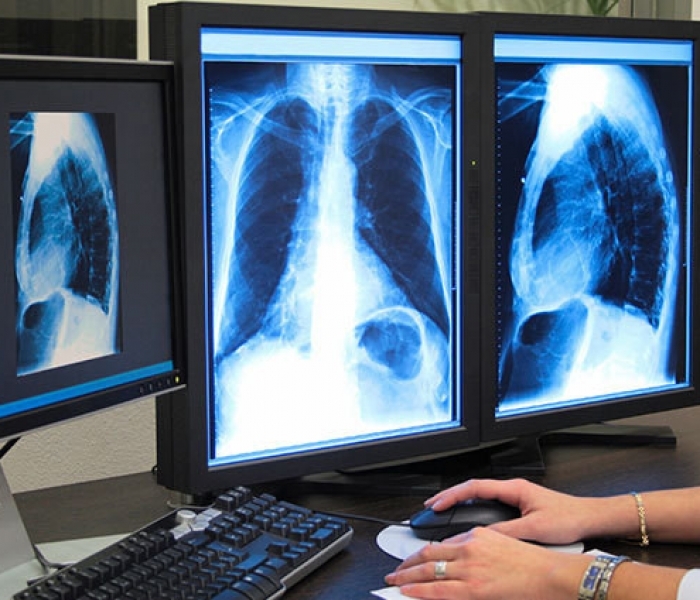

В поликлиниках Москвы внедряется новый бесплатный метод ранней диагностики рака легких у курильщиков с помощью низкодозной компьютерной томографии. Пилотный проект уже прошел апробацию, сообщили "РГ" в пресс-службе департамента здравоохранения столицы.

Программа низкодозной компьютерной томографии грудной клетки разработана Научно-практическим центром медицинской радиологии департамента здравоохранения Москвы и стартовала в 2017 году. Направление на скрининг можно получить у терапевта, участкового врача или врача общей практики в городской поликлинике по полису ОМС. Результаты скрининга каждого пациента вносятся в общую городскую базу (Единый радиологический информационный сервис и затем в ЕМИАС) и доступны врачам поликлиник. При необходимости пациента направят на дополнительные обследования или консультации специалистов, в том числе врача-онколога.